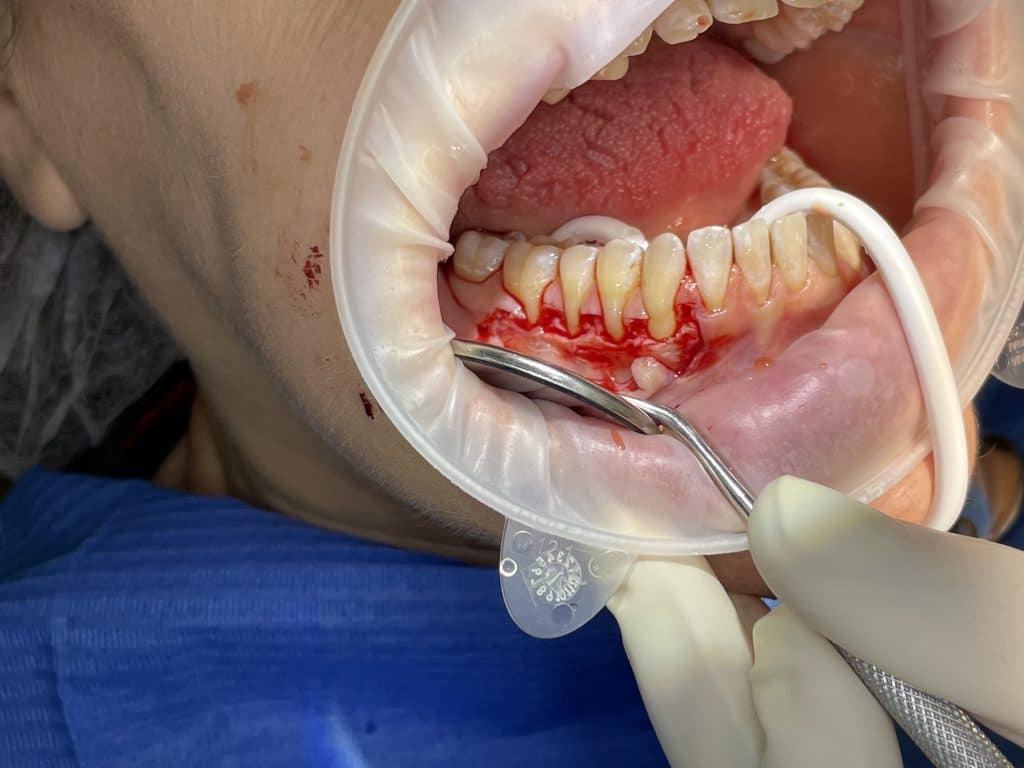

In quadrant 4, we initially proceeded with the reconstruction of the cervical part of the teeth and, where present, the removal of caries. Subsequently, we performed a bilaminar technique for multiple gingival recessions using a trapezoidal-shaped flap and minimal relieving incisions. We harvested a connective tissue graft from the palate, which was sutured to the periosteum and then covered with the coronally advanced flap, following the bilaminar technique. The sutures were removed after 10 days.

paramarginal incision

full and split thickness flap